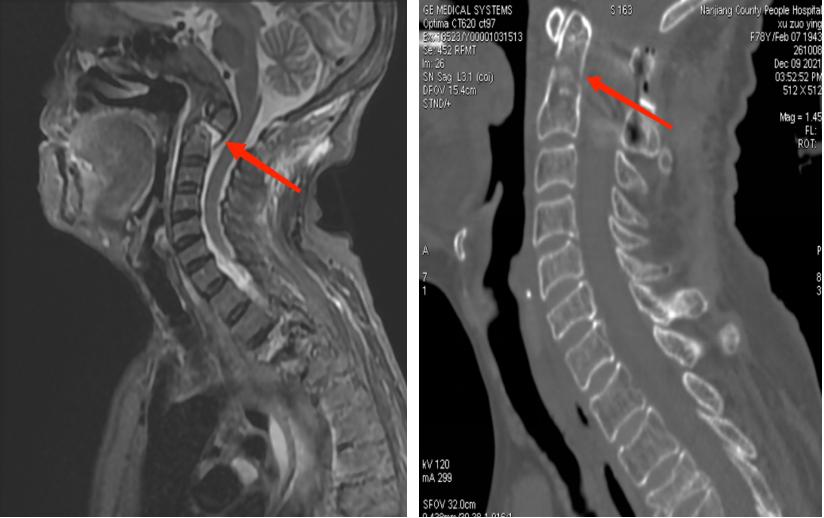

庆幸的是,面对患者及家属的信任和期待,南江县人民医院骨科医师团队在做好充分的术前准备后于12月8日成功为患者实施了手术。术后,许奶奶的寰枢椎脱位完美复位,疼痛及肢体麻木等症状都得到明显缓解,目前,许奶奶病情平稳,已经能佩戴头颈支具下地行走,日常生活能力也在进一步康复中。“如果不是南江县人民医院,如果不是张医生,我母亲可能会卧床一辈子了”,许奶奶的女儿激动地说。

图为术后CT显示